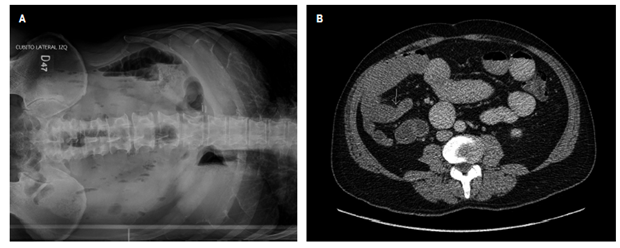

Se presenta el caso de un hombre de 65 años sin antecedentes previos, que consultó por un cuadro de 24 horas de evolución de dolor y distensión abdominal generalizada asociada con vómito en “cuncho de café” documentándose obstrucción intestinal en radiografía simple de abdomen, que se confirmó en la tomografía con cambios estructurales inespecíficos en asas ileales distales, sin signos de sufrimiento de asa (Figura 1). En los paraclínicos complementarios se identificó la presencia de anemia microcítica hipocrómica, por lo que se volvió a interrogar al paciente y refirió episodios previos aislados de melenas con estudios de endoscopia de vías digestivas altas y colonoscopia total sin evidencia de lesiones patológicas.